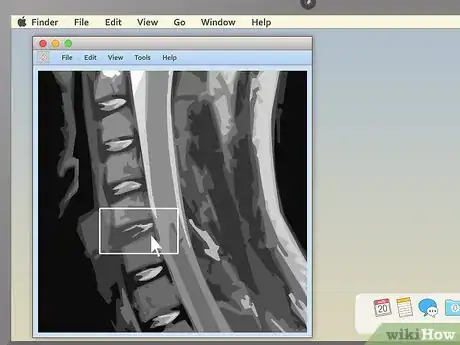

2. 2

Examine the structure of the vertebrae for spinal MRIs. MRIs of the spine are typically some of the easiest for non-doctors to read (especially in sagittal view). Look for noticeable misalignments in the vertebrae or fluid discs. Having just one of either be out of alignment (as in the example above) can be the source of serious pain.

• Behind the spinal vertebrae, in sagittal view, you'll see a white, rope-like structure. This is the spinal cord, the structure connected to all the body's nerves. Look for spots where the vertebrae or discs seem to "pinch" or press into the spinal cord — because the nerves are so sensitive, just a little pressure can lead to pain.